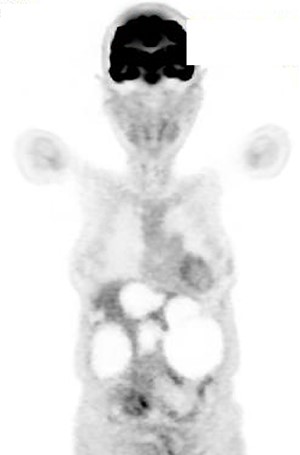

A 74-year-old woman presented with right upper abdominal pain and poor dietary intake. She had no notable medical history or history of abdominal trauma. Abdominal computed tomography (CT) showed multiple liver cysts, with the size of the largest cyst in the right lobe measuring 155 × 113 × 106 mm (Fig. 1a). In addition, a large cyst measuring 135 mm in the left lateral lobe strongly compressed the stomach (Fig. 1b). T1-weighted magnetic resonance imaging revealed different findings in the right and left lobe cysts, and there were no enhanced structures in the liver cysts (Fig. 2). Positron emission tomography-CT did not show increased 18F-fluorodeoxyglucose metabolism in any of the liver cysts (Fig. 3). Moreover, hepatobiliary scintigraphy with CT showed no biliary communication with the liver cysts (Fig. 4). The patient was diagnosed with symptomatic and multiple liver cysts with no biliary communication or malignancy. Therefore, LF was performed.

Positron emission tomography-CT showing no increase in 18F-fluorodeoxyglucose metabolism in the liver cysts.